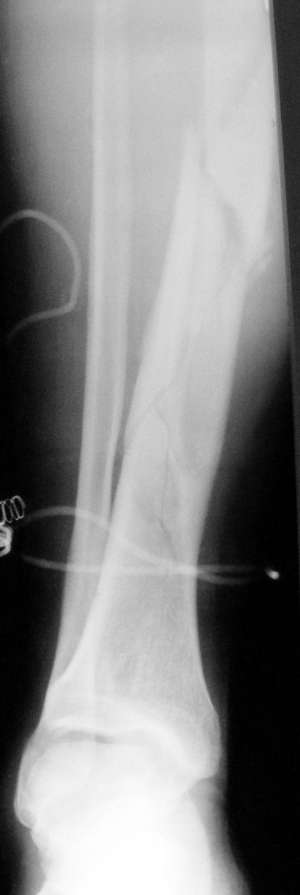

перелом большеберцовой кости

больной 30ти лет получил травму в быту, подвернул левую голень.

На данный момент на скелетном вытяжении.рентген снимки прилагются.Какие будут у вас мнения по поводу остеосинтеза. Были ли у вас подобные случаи и какие методы вы бы предложили.

здравствуйте Алексей. ситуация не простая. в данном случае мы имеем многооскольчатый перелом б\берцовой кости. помогать надо. можно применить малоинвазивный синтез в виде пластины с угловой стабильностью. восстановить длину конечности и ось. на самом переломе можно не вмешиваться положить мостовидно. если у Вас нет такой технологии то как минимум поправить вытяжение. думать об интрамедуллярной фиксации я бы не советывал. Удачи.

здравствуйте. но рентгенограмме не видно проксимального отдела большеберцовой кости, если там повреждений нет, то почему так категорично против БИОС? На мой взгляд вполне возможно заштифтовать закрыто. кстати, перелом закрытый или открытый?

В условиях "виртуальной" ЦРБ, обсуждаемой в данном топике, однозначно я рекомендовал бы аппарат Илизарова. В нижней трети голени репозиция отломков контролируется пальпаторно, что делает ненужным применение ЭОП, столь необходимого для БИОС. Если говорить о пластине, то из-за отсутсвия мышц на данном участке возможно лишь применение низкопрофильных конструкций с угловой стабильностью, вряд ли доступных в ЦРБ.На прилагаемых рентгенограммах аппарат Илизарова наложенный практический "вслепую" (1 рентгенконтроль в конце операции).